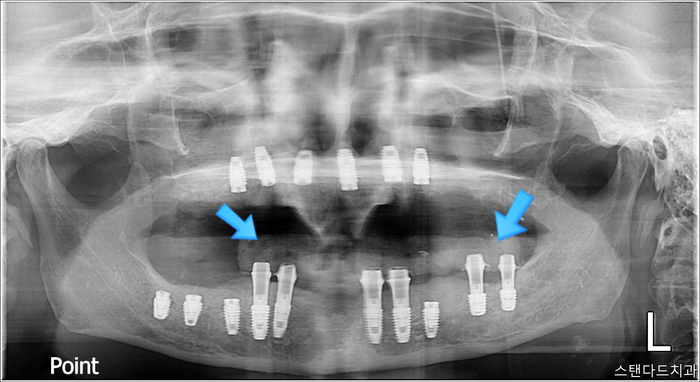

1차 수술 진행

촬영:2024년1월23일

치과 공포증과 통증을 줄여드리기 위해 치과수면마취로 진행했고

발치→뼈이식+상악동거상술→

임플란트(16개)식립→임시치아 까지

당일 진행되었으며 수술은 약 3시간 소요되었습니다.

상악의 경우에는 임시전체틀니를 해드렸고

하악에 임시치아를 일부분만 올려드렸는데

2차 임플란트 수술

촬영:2024년8월27일

처음 수술 후 8개월이 지났습니다.

원래는 3-4개월이면 2차 수술을 진행하지만

(사진상오른쪽) 기존에 있었던 자연치아인 끝 어금니

두 개가 뿌리 안쪽으로 염증이 깊다 보니

그만큼의 골소실도 많고 상악동 바닥을 염증이 뚫어서

바로 뼈이식을 하지 못하고 염증 치료를 먼저 진행하고

상악동거상술로 잇몸뼈를 채웠는데

원래도 단단하지 못한 상악인지라

최대한 시간을 갖고 고정력이 나올 수 있을 때까지 기다려서

8개월의 충분한 시간을 기다린 후

임플란트를 식립하였습니다.